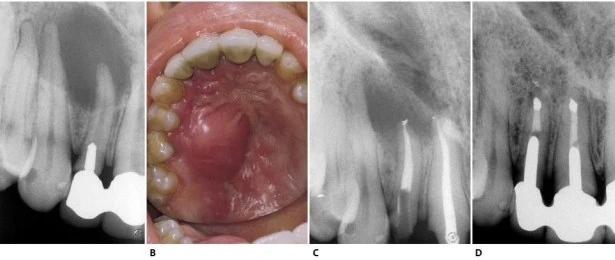

Hình 8.21. A.Phim sau điều trị của răng cửa bên hàm trên bên trái. Hình dạng và góc đọ của thấu quang, đường viền rõ và với kích cỡ của một nang. B. Sưng ở vùng khẩu cái. C. Hình ảnh mô học của tổn thương (×2,5). D. Phóng đại lớn, tổn thương mang những đặc trưng của u hạt (×250). E. Phim sau điều trị. Việc trám ngược được thực hiện ở răng cửa giữa bên phải. F. Một năm sau. Lưu ý rằng “sẹo quanh chóp” lớn vài mm phía trên chân răng cửa bên.

Hình 8.27. Phim Xquang trước điều trị của răng của bên hàm trên bên phải cho thấy hình ảnh tổn thương dạng nang lớn. Răng nanh và răng cối nhỏ đáp ứng dương tính với test thử tủy sống, trong khi đó răng cửa giữa cho kết quả âm tính. B. Một áp xe cấp tính lớn ở vùng xương ổ răng đã phát triển do một tổn thương mạn tính và nó thấy được ở vùng khẩu cái. C. Phim sau điều trị. D. Tám năm sau phẫu thuật cắt chóp. Do các triệu chứng sưng cấp tính tái diễn (có lẽ liên quan đến việc trám bít vùng chóp không đủ do gặp khó khăn khi làm khô ống tủy), cắt chóp và trám ngược bằng amalgam được thực hiện ở răng cửa giữa và răng cửa bên.